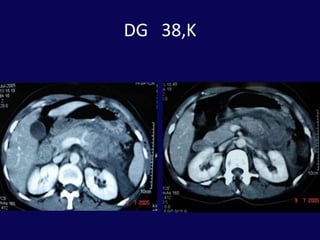

SK 6,E20 Gün önce bisikletten düşme dış merkezde taip batın distansiyonu gelişmesi üzerine İTF ne sevkFM: Distansiyon ve yaygın hassasiyet

BT: pankreas orta hatta laserasyon ve peripankreatik sıvı

Hasta işlem sonrası 23. gününde ateş, bulantı, kusma şikayetleriyle yeniden yatırıldı.BT’ de karaciğer ve mide arasında 6x5 cm’lik bir koleksiyon tespit edildi. Perkütan drenaj uygulandı. 200 cc geleni oldu.